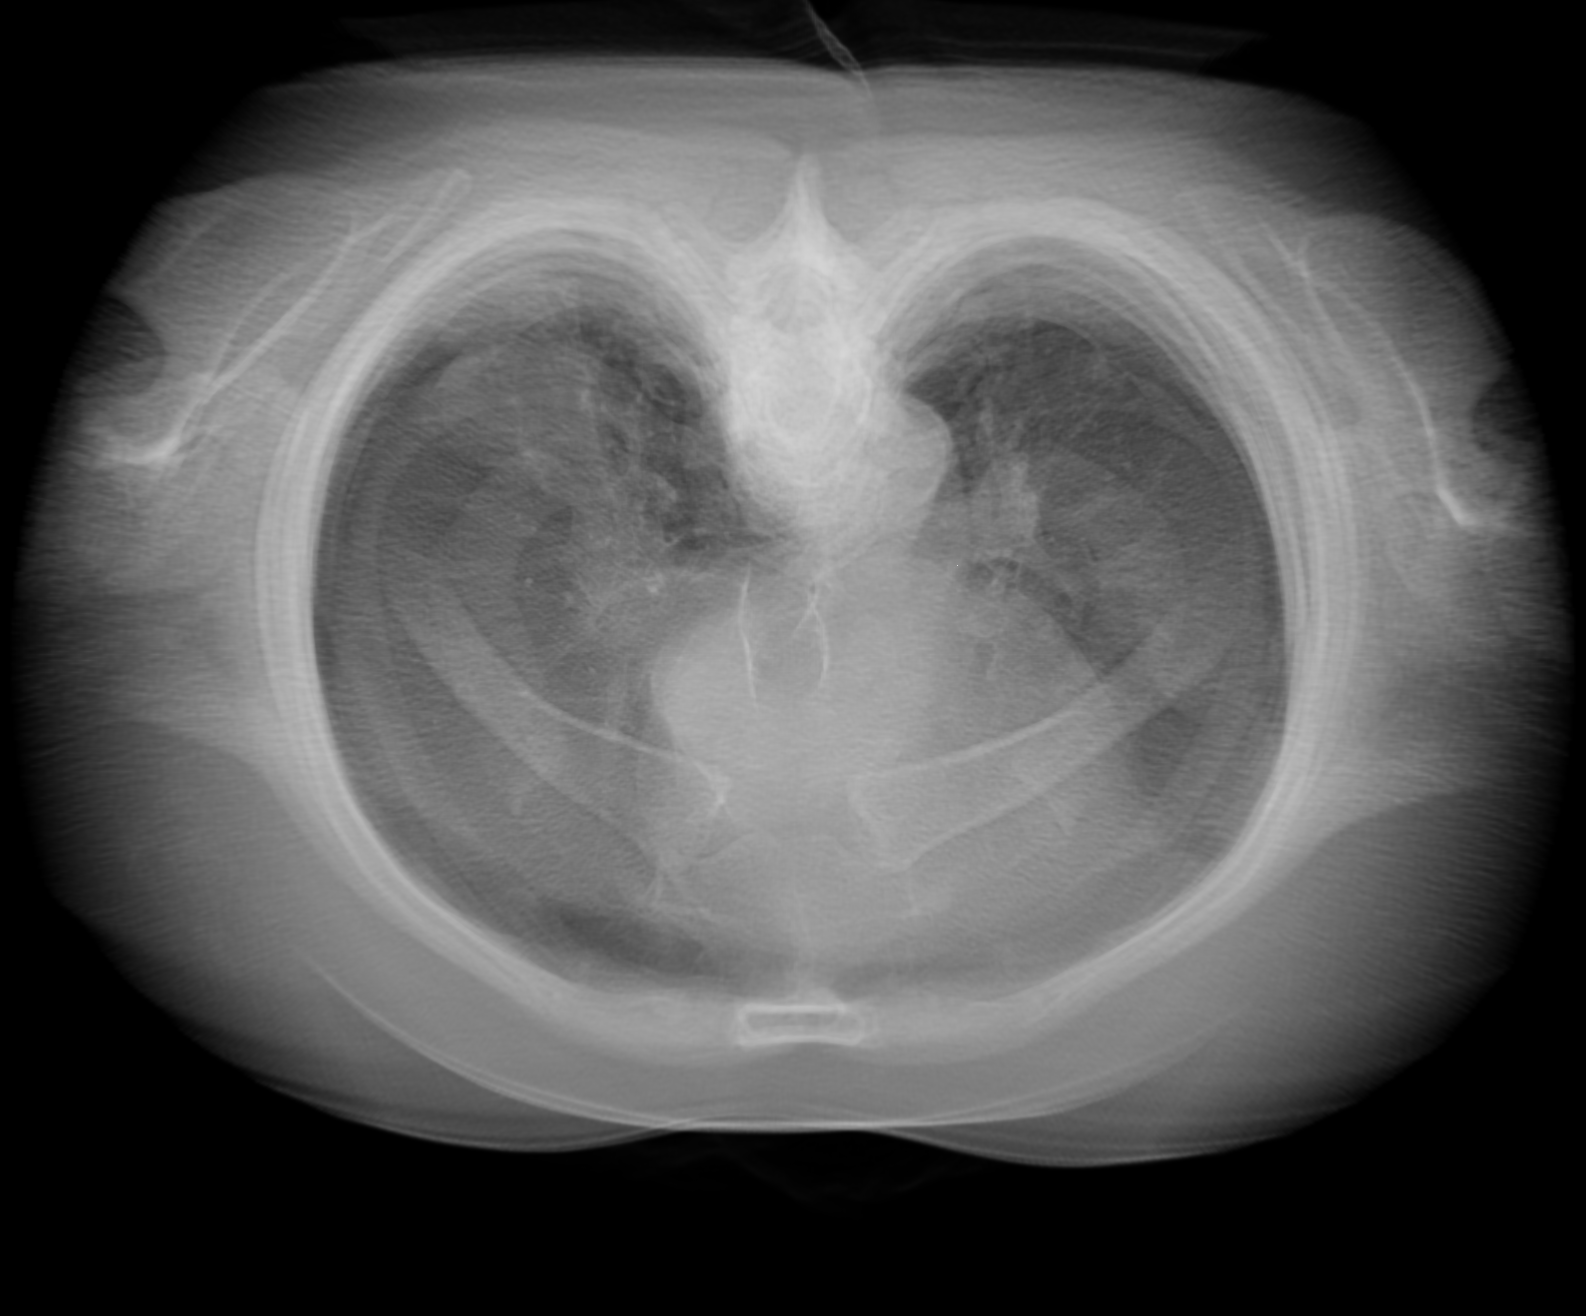

step1-8bit.png (1.3 MB ) - added by Tom Goddard 7 years ago.

DICOM lung CT 512x512x236 step 1 folder 4-24533, normal 8-bit rendering

I attached 6 example images of a lung CT scan (folder 4-24533), grid size 512 x 512 x 236, 3d projection rendered with plane spacing minimum along 3 axes, voxel size .576 x .576 x 1.25, so about 500 planes, view along z axis, perspective projection. Step 1 and 2 look quite different with normal 8-bit rendering, but look nearly the same with 16-bit rendering. Both 16-bit framebuffer and 16-bit color/alpha texture contribute have significant effect on the appearance.